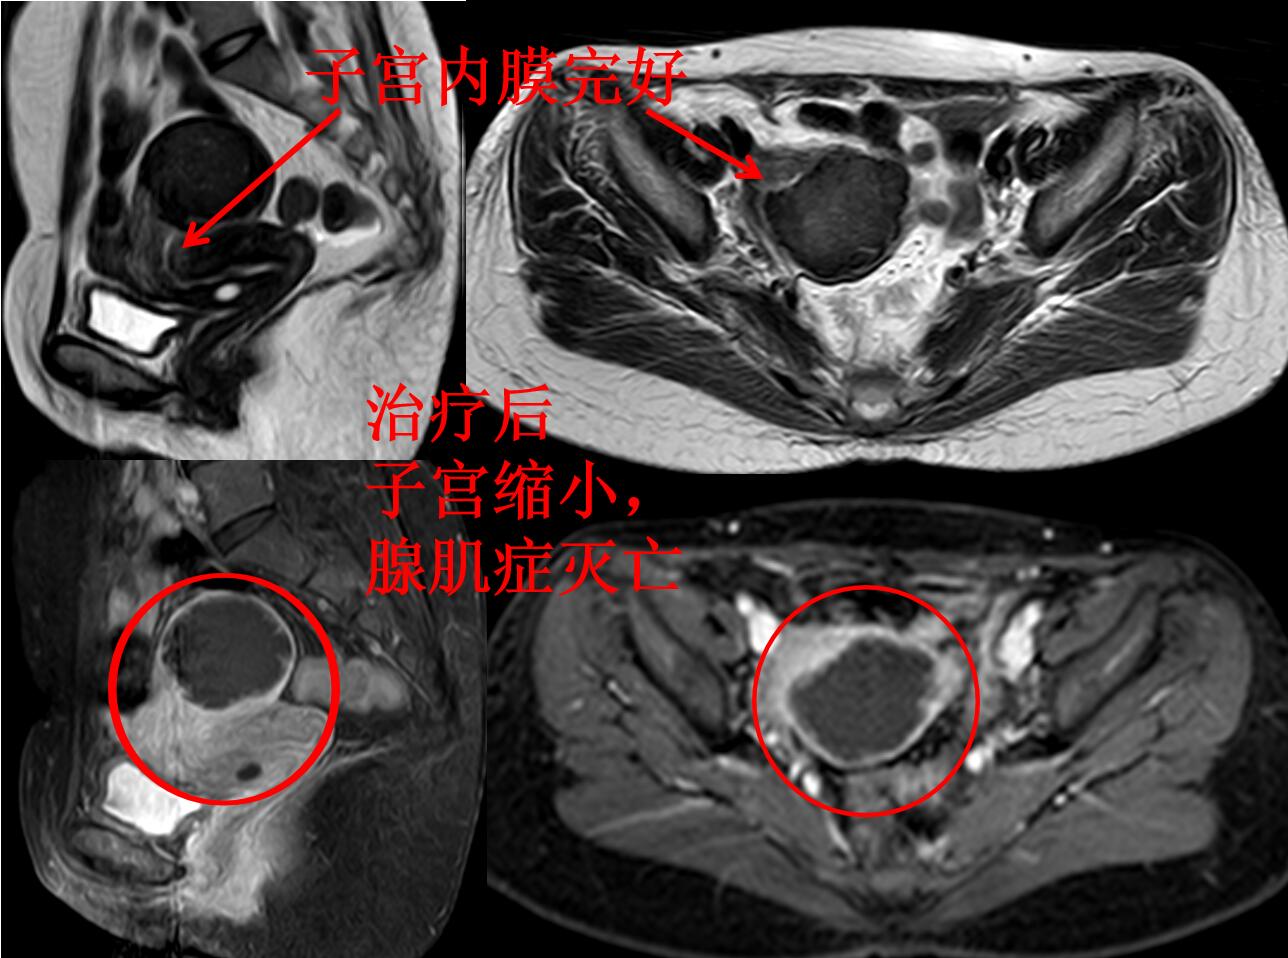

介入微创消融治疗后无明显痛经,3个月后复查磁共振显示:子宫腺肌病病灶灭亡,子宫缩小(如下图)。

介入微创消融治疗后1年痛经没法复发,复查磁共振显示:子宫大小恢复正常,腺肌症灭亡吸收排出(如下图)。